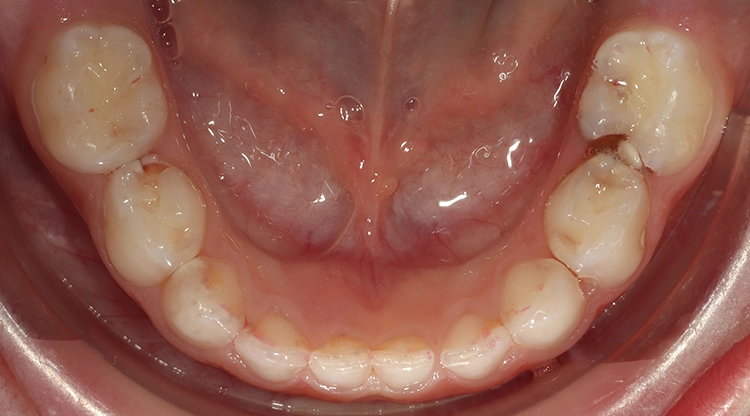

Ein 4-jähriges mäßig kooperatives Kind erscheint zur Kontrolle in der Zahnarztpraxis. Bei der klinischen Untersuchung sind offensichtlich zwei (scheinbar kleinere) approximal kavitierte kariöse Läsionen im Unterkiefer zu sehen sowie Läsionen an den Oberkieferschneidezähnen (Abb. 1a und b). Eine Versorgung dieser Zähne scheint nach klinischer Untersuchung bei diesem Kind noch ambulant möglich.

Erst eine weitergehende röntgenologische Untersuchung zeigt das ganze Ausmaß des Kariesbefalls (Abb. 1c). Das Kind wies an fast allen Milchzähnen bereits Dentinkaries, zum Teil auch schon sehr tiefe Läsionen (Zahn 75), auf. Solch ein Befund scheint bei zahlreichen konventionell-restaurativen Maßnahmen bei altersentsprechender mäßiger Kooperation (fast) nur in Narkose behandelbar.

Beim Kleinkind spielt primär die frühkindliche Karies eine Rolle, die initial meist durch kariöse Läsionen an den Oberkieferfrontzähnen gekennzeichnet ist (Abb. 2). Im permanenten Gebiss unterliegen die Kauflächen der durchbrechenden 1. und 2. Molaren insbesondere in der ca. 1,5 Jahre dauernden Durchbruchsphase einem erhöhten Kariesrisiko. Während kieferorthopädischer Maßnahmen mit festsitzenden Apparaturen bei Jugendlichen sollte besonderes Augenmerk auf die Beurteilung der Mundhygiene, wie dem Vorhandensein kariogener Plaque auf Kariesrisikoflächen (Abb. 3), und Kariesaktivität gelegt werden, um frühzeitig präventiv einzugreifen und klinische Bilder mit kariösen Läsionen an fast allen Zähnen möglichst zu vermeiden (Abb. 4).